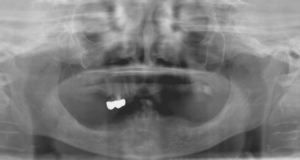

インプラント義歯 ミニインプラント症例

術前術前主訴-総入れ歯の安定が悪い 即時加重可能のミニインプラント使用した。 術前レントゲン術前レントゲン術前レントゲン CT撮影から3次元骨モデルを作成CT撮影から3次元骨モデルを作成CT撮影から3次元骨モデルを作成し埋入位置の確認 フィクスチャーを浸潤麻酔下で埋入フィクスチャーを浸潤麻酔下で埋入。歯茎を切らないので患者さんも非常に楽

4本埋入終了4本埋入終了4本埋入終了(このシステムは4本が絶対条件) 義歯の調整義歯の調整当日に義歯の調整に取りかかる。裏側より義歯をくりぬき維持部のカバー(ハウジング)を義歯の内面に埋め込む step1 義歯の調整義歯の調整当日に義歯の調整に取りかかる。裏側より義歯をくりぬき維持部のカバー(ハウジング)を義歯の内面に埋め込む step2 義歯の調整当日に義歯の調整に取りかかる。裏側より義歯をくりぬき維持部のカバー(ハウジング)を義歯の内面に埋め込む step3

義歯の調整義歯の調整当日に義歯の調整に取りかかる。裏側より義歯をくりぬき維持部のカバー(ハウジング)を義歯の内面に埋め込む step4 義歯の調整義歯の調整当日に義歯の調整に取りかかる。裏側より義歯をくりぬき維持部のカバー(ハウジング)を義歯の内面に埋め込む step5 義歯の裏側義歯の裏側義歯の裏側 装着後しっかり噛める様になる

術後レントゲン術後レントゲン術後レントゲン